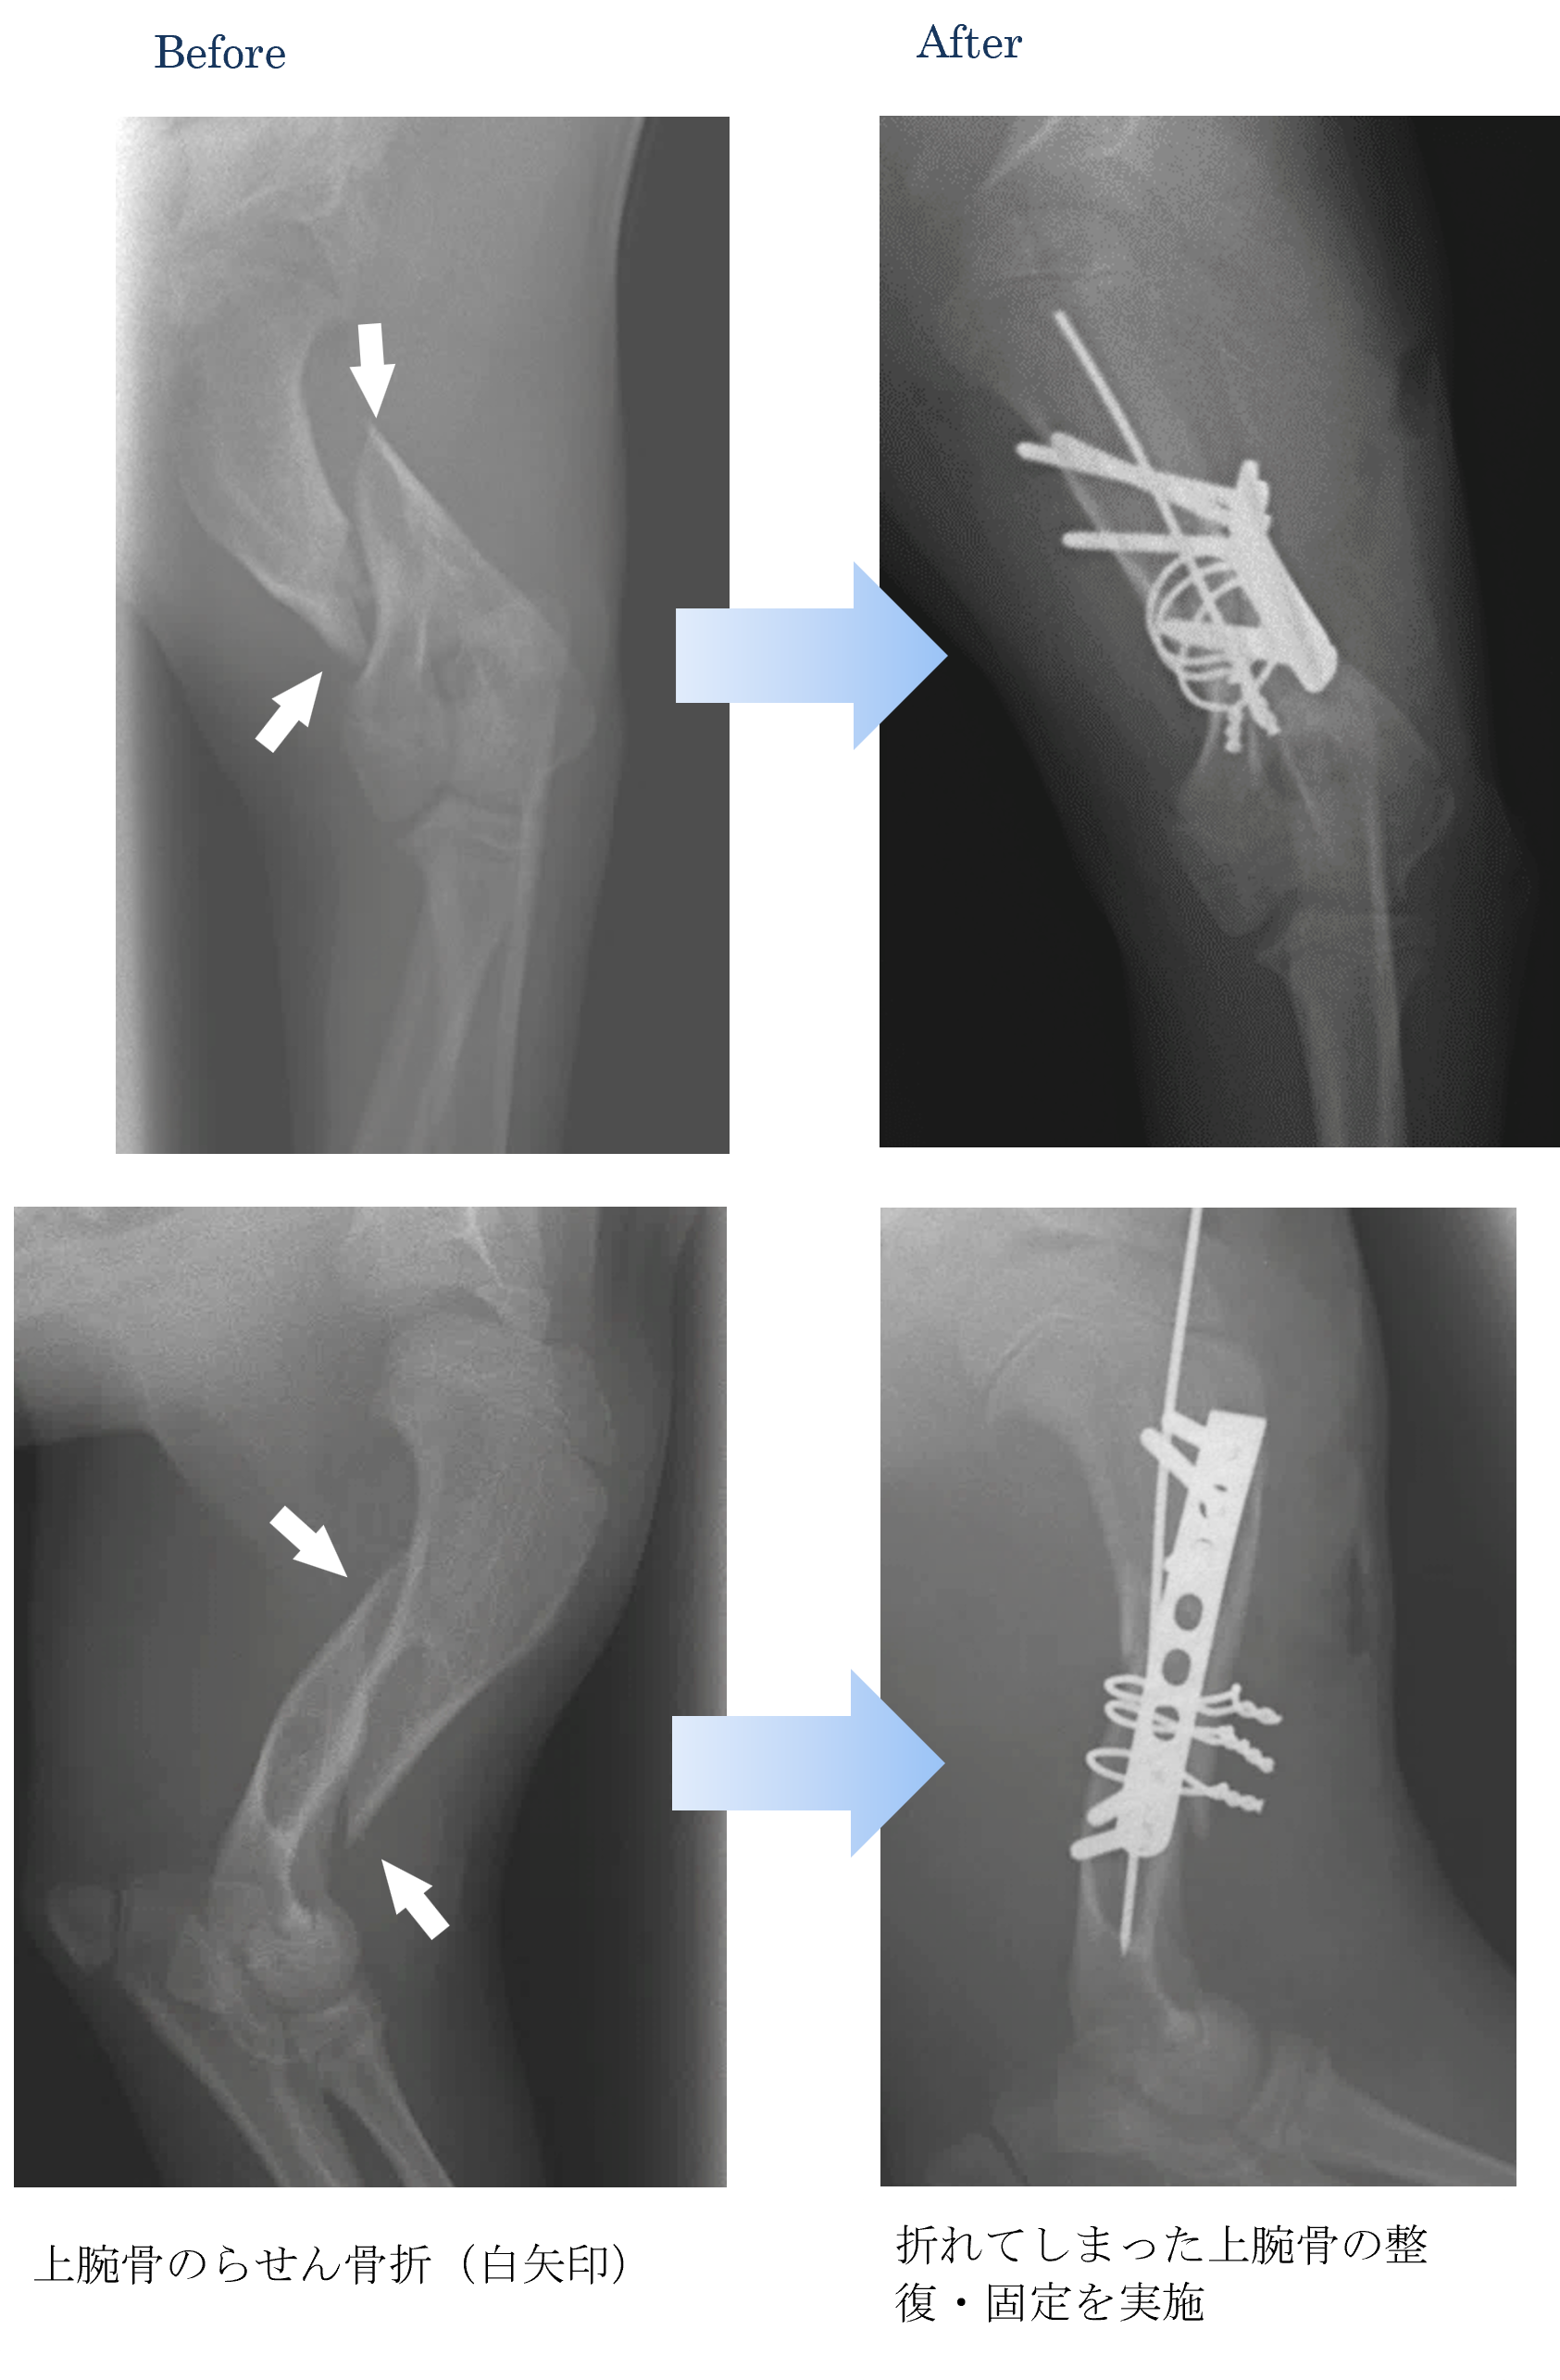

各種検査より、上腕骨(腕の骨)の骨折と診断しました。

ご家族と相談した結果、手術による骨折の整復および固定を実施することになりました。

術後も順調で走り回るくらいに元気になりました。